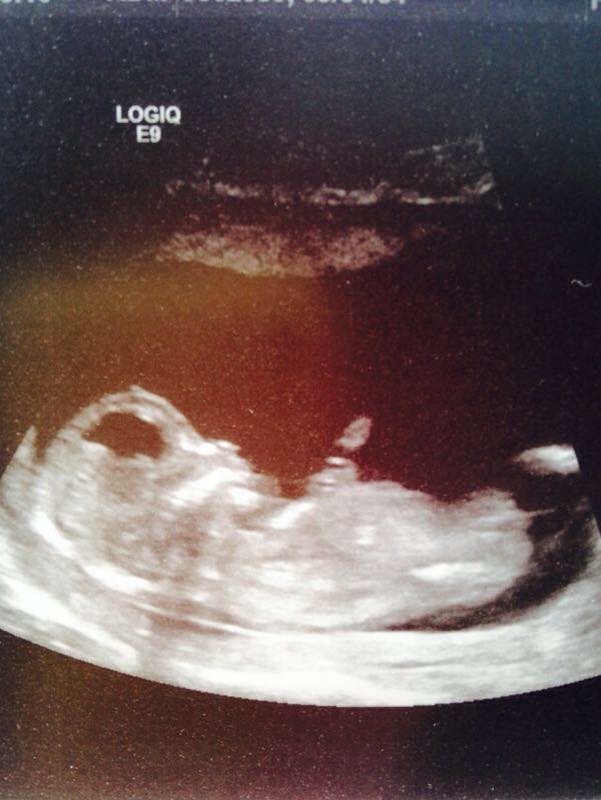

Yes!!!! Looking verrrry GIRLY!!!

looks girly to me too....fingers crossed for you!!!

Leaning Girl :)

girl

Looks to early. How far along were you when scan was taken?